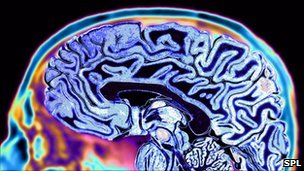

Writing in the journal Nature, researchers said they have developed a system capable of recording higher-level brain activity.